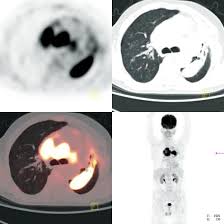

The researchers found 2,185 potentially misdiagnosed copd patients who died less than a year after their diagnosis. Malignant tumors trigger inflammation in surrounding normal lung tissue, and they may obstruct your airways and interfere with normal airflow. In lung cancer, lung cells exhibit abnormal and uncontrolled growth starting the lungs, while asthma is caused by inflammation and/or mucus that decreases or blocks the breathing passages (bronchioles) of the lungs. Lung cancer is a general term that includes all abnormal lung tissue cells that multiply unregulated and form tumors or growths in the lungs.these tumor cells may spread (metastasize) to other parts of the body.; Various organs can be affected including the skin, lymph nodes, and liver. When sarcoidosis affects the lungs, symptoms can mimic idiopathic pulmonary fibrosis including shortness of breath and a dry cough. Pancreatic cancer may also be misdiagnosed as gallstones or pancreatitis, or the inflammation of the pancreas. Chronic obstructive pulmonary disease (copd) is a serious lung condition found mostly in smokers. How copd can trigger the onset of lung cancer is not entirely clear but, as a group of progressive obstructive diseases —which includes chronic bronchitis and emphysema)—copd is known to cause profound and irreversible changes to the airways. Chronic obstructive pulmonary disease (copd) and emphysema have been described as possible risk factors for lung cancer. This can lead to misdiagnosis as conditions such as irritable bowel syndrome (ibs). This test can also be used to look for masses in the adrenal glands, liver, brain, and other organs that might be due to the lung cancer spread. However, it can occur in other heart and lung diseases.